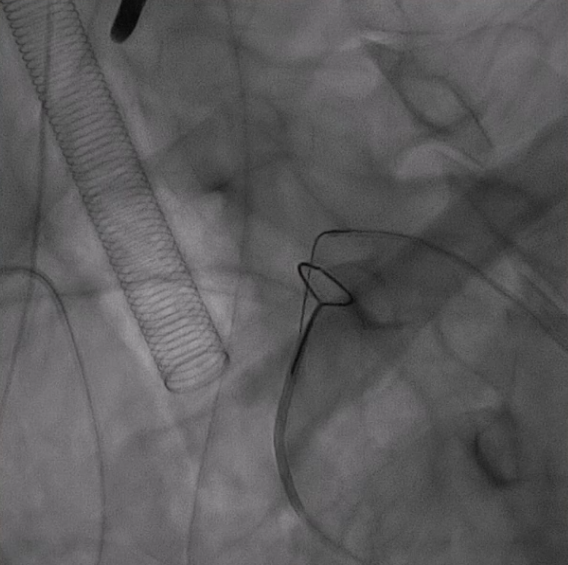

从右侧股动脉入路,使用超滑导丝进入真腔,置入金标猪尾导管造影,再次造影明确夹层真腔位置、形态,可见腹主动脉及降主动脉真腔处多处严重狭窄受压,假腔呈瘤样扩张并累及左侧锁骨下动脉。

通过左侧股动脉入路置入猪尾导管,并在超硬导丝引导下置换24F大鞘,缓慢送入防缠绕导管至主动脉弓部。

3. 关键分支处理环节,分支导丝超选与抓捕建立分支导丝通路

使用4F 导管和抓捕系统,分别超选弓上三分支(无名动脉、左颈总、左锁骨下动脉)

14系统导丝经防缠绕导管引出至右侧股动脉输送鞘外,建立分支导丝通路。

无旋转状态下撤出防缠绕导管。